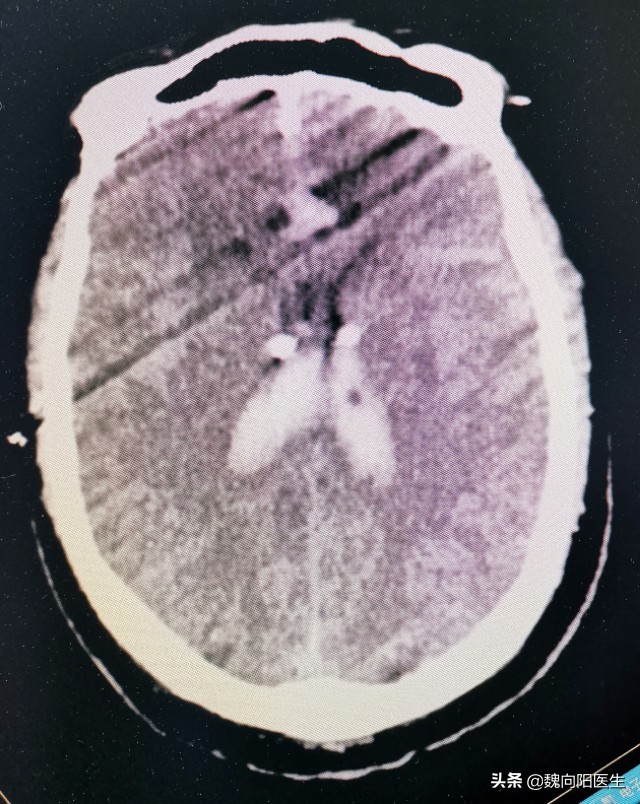

但是他的脑室却越来越大,血少了,但是水多了,学名叫做《脑积水》。

蛛网膜下腔出血后,在蛛网膜下腔中充满了血液。尤其是出血量较大时,凝血块可以阻塞脑室与外部的通道,而且陈旧的血液封闭了脑脊液吸收结构——蛛网膜颗粒。导致脑室内不断生成的脑脊液有流不出来,甚至蛛网膜颗粒回收减少或不能回收,于是造成脑室“水增加”,引起脑室扩大,这就是脑积水。

- 蛛网膜下腔出血的恢复期,因为蛛网膜颗粒脑积液回收障碍,从而导致脑室内脑脊液便增加,从而使脑室变大,行成慢性脑积水。